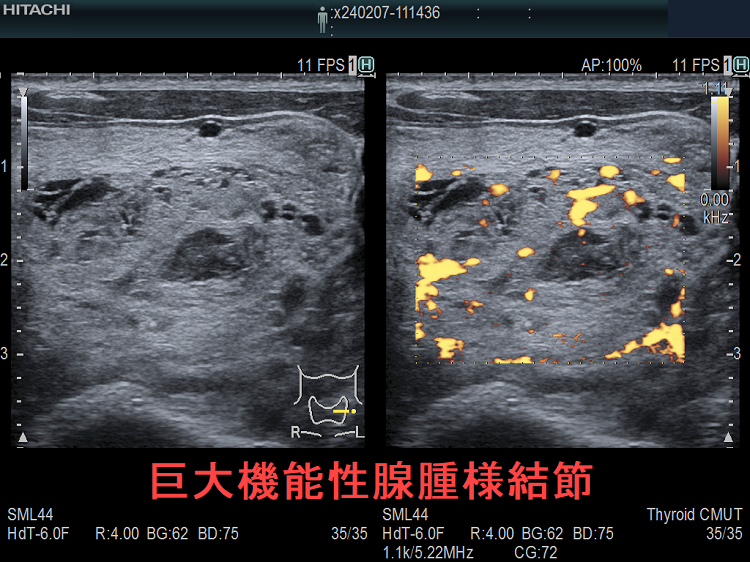

医師が多結節性甲状腺腫を発見した場合、甲状腺の超音波検査を受けることになるでしょう。超音波検査の結果に応じて、結節に癌性があるかどうかを確認するために細針吸引生検が行われる場合があります。

したがって、医師は甲状腺超音波検査を指示する場合があります。超音波検査では、音波を使用して甲状腺の写真を撮影します。これは、医師が結節が体液で満たされているか、石灰化があるかを判断し、結節の数と場所を確認し、癌の可能性がある結節を特定するのに役立ちます。